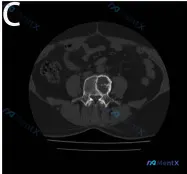

整理到一份腰椎影像学病例资料,先放核心信息出来: 基础影像表现: - 腰椎椎体(L4)可见明显溶骨性骨质破坏,左侧椎体后缘及侧缘骨皮质连续性中断 - 椎体内部骨小梁结构紊乱,病灶边缘模糊,未见明确骨膜新生骨 - 椎体形态改变,左侧轮廓向外膨出,后缘向椎管内突入,疑似软组织肿块影占据椎管左侧区域 -...